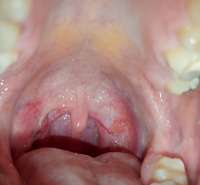

Всем привет, вот такую припухлость сильную обнаружил у себя в горле после болезни, сходил к двум лор врачам, они сказали, что это остатки миндалены, тип не полностью удалили, завтра иду сдавать гистологию, на всякий случай. Аноны, это похоже на рак? Не курю, не пью. И больно ли сдавать гистологию? Лимфоузлы не увеличины, один лор назначил лечение, спустя неделю она немного уменьшилась, рак может уменьшаться? Но прям совсем немного